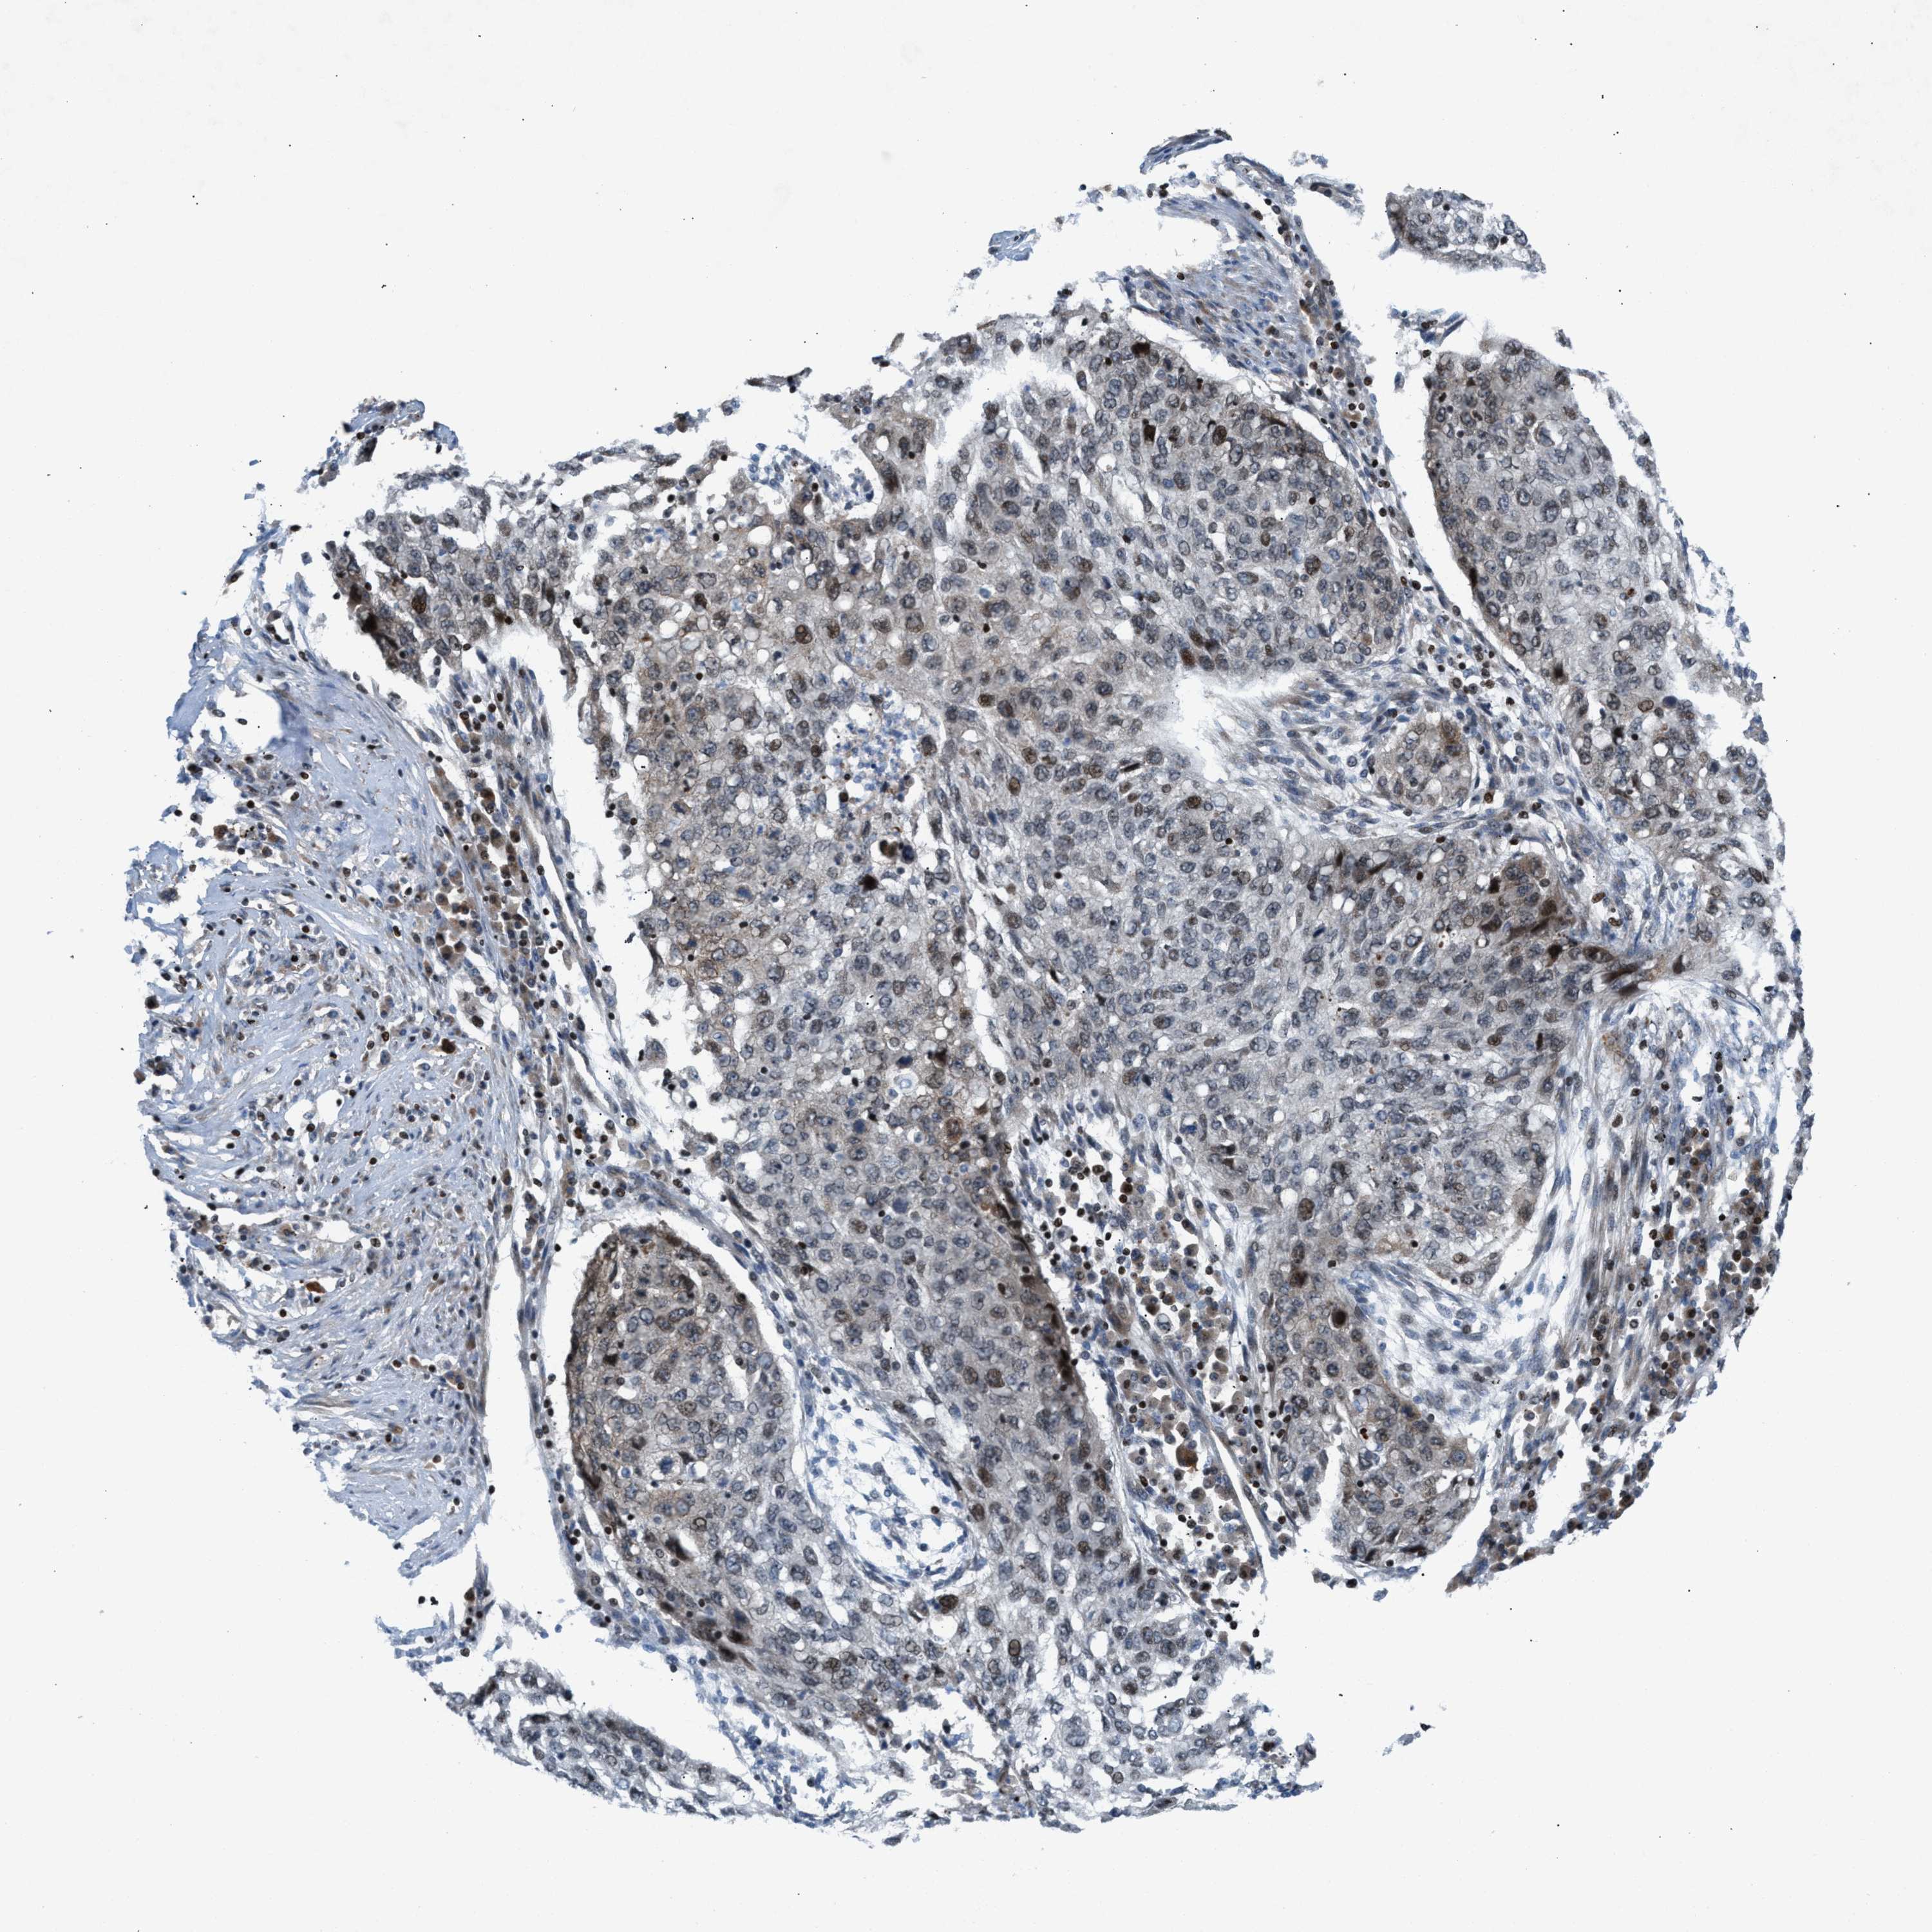

LUNG ADENOCARCINOMA (VALIDATION) - Interactive survival scatter ploti

The Survival Scatter plot shows the clinical status (i.e. dead or alive) for all individuals in the patient cohort, based on the same data that underlies the corresponding Kaplan-Meier plots. Patients that are alive at last time for follow-up are shown in blue and patients who have died during the study are shown in red.

The x-axis shows the expression levels (FPKM) of the investigated gene in the tumor tissue at the time of diagnosis. The y-axis shows the follow-up time after diagnosis (years). Both axes are complimented with kernel density curves demonstrating the data density over the axes. The top density plot shows the expression levels (FPKM) distribution among dead (red) and alive patients (blue). The right density plot shows the data density of the survived years of dead patients with high and low expression levels respectively, stratified using the cutoff indicated by the vertical dashed line through the Survival Scatter plot. This cutoff is automatically defined based on the FPKM cutoff that minimizes the p-score. The cutoff can be changed by dragging the vertical line or by entering a cutoff value in the square labeled "Current cut-off".

Under the Survival Scatter plot the p-score landscape (black curve; left axis) is shown together with dead median separation (red curve; right axis). Dead median separation is the difference in median mRNA expression between patients who have died with high and low expression, respectively. It is calculated as follows: median FPKM expression of dead patients with high expression - median FPKM expression of dead patients with low expression. This is intended to aid the user in visually exploring custom cutoffs and the associated p-scores and dead median separation.

Individual patient data is displayed and can be filtered by clicking on one or more of the category buttons on the top of the page. Categories describing expression level and patient information include: high, low, alive, dead, female, male and tumor stages. The scale of the x-axis can be toggled between linear and log-scale by clicking on the "x log" button. Mouse-over function shows TCGA ID, patient information and mRNA expression (FPKM) for each patient.

& Survival analysisi

Kaplan-Meier plots summarize results from analysis of correlation between mRNA expression level and patient survival. Patients were divided based on level of expression into one of the two groups "low" (under cut off) or "high" (over cut off). X-axis shows time for survival (years) and y-axis shows the probability of survival, where 1.0 corresponds to 100 percent.

ZNF276 is not prognostic in Lung Adenocarcinoma (validation)

Best expression cut offi

Based on the FPKM value of each gene, patients were classified into two groups and association between prognosis (survival) and gene expression (FPKM) was examined. The best expression cut-off refers the FPKM value that yields maximal difference with regard to survival between the two groups at the lowest log-rank P-value. Best expression cut-off was selected based on survival analysis .

When clicking on this number, the vertical dashed line indicating cut-off, the interactive survival plot, and the Kaplan-Meier curve will be adjusted to show results based on the best expression cut-off.

: 4.59

Median expressioni

Median expression refers to the median FPKM value calculated based on the gene expression (FPKM) data from all patients in this dataset. When clicking on this number, the vertical dashed line indicating cut-off, the interactive survival plot, and the Kaplan-Meier curve will be adjusted to show results based on the median expression.

: N/A

Median follow up timei

Median follow up time refers to the median time (years) after diagnosis with this type of cancer, based on clinical data from all patients in this dataset.

P scorei

Log-rank P value for Kaplan-Meier plot showing results from analysis of correlation between mRNA expression level and patient survival.

N/A

5-year survival highi

5-year survival for patients with higher expression than the expression cutoff.

For melanoma and glioma, 3-year survival is shown.

5-year survival lowi

5-year survival for patients with lower expression than the expression cutoff.

TCGA RNA samplesi

RNA-seq data is reported as average FPKM (number Fragments Per Kilobase of exon per Million reads), generated by the The Cancer Genome Atlas (TCGA) .

Normal distribution across the dataset is visualized with box plots, shown as median and 25th and 75th percentiles. Points are displayed as outliers if they are above or below 1.5 times the interquartile range. FPKM values of the individual samples are presented next to the box plot.

Average pTPM 5.5

Number of samples 105